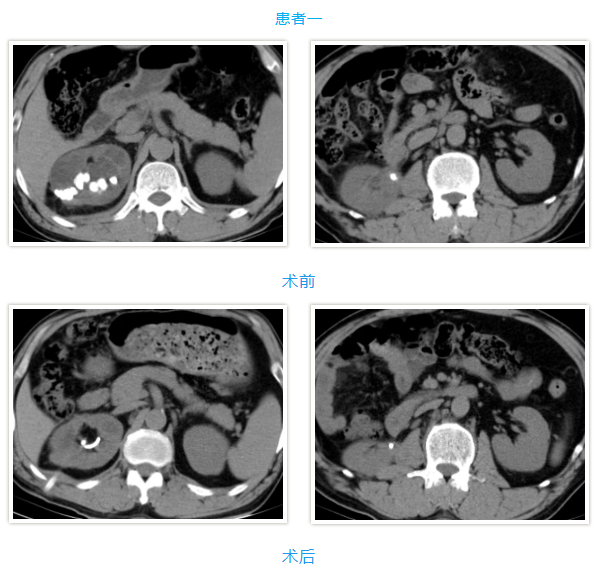

两名患者均为中年男性,入院检查发现肾内多发铸型结石,结石体积大、分布广,其中一例既往患肾行开放取石及经皮肾取石手术,盏颈狭窄伴有肾积水;另一例无明显积水,净石难度高。传统开放手术创伤大、恢复慢,单一微创技术难以彻底清除结石。针对患者病情,泌尿外科团队高度重视,多次组织病例讨论,结合患者身体状况与手术耐受度,最终制定“经皮肾镜+输尿管软镜”联合微创治疗方案。

在泌尿外科团队及麻醉科团队成员密切配合。患者取斜仰截石位,先通过输尿管软镜探查输尿管及肾盂肾盏情况,精准定位结石;随后在超声引导下建立经皮肾通道,置入经皮肾镜,利用钬激光碎石设备将复杂结石击碎成细小颗粒,部分结石因角度问题经皮肾镜无法够到,则通过软镜配合取石篮将结石拖入经皮肾通道口进行彻底清除。整个手术过程创伤小、出血少,术后患者恢复顺利,未出现相关并发症,现已康复出院。